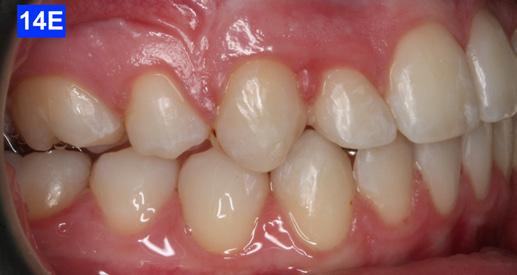

Figure 1E: Pre-treatment, right lateral view

Figure 1F: Pre-treatmrnt, left lateral view

Clinical Micro-esthetic appraisal revealed Angle Class I molar relationship. The arches were narrow, there was crowding, and she had a posterior crossbite. The patient had 2.0 mm overjet and 1.5 mm overbite. There was an anterior cross bite on #12(7) and #22(10), which indicates Class III tendency. The lower airway was very narrow, only 5.0 mm; however, the patient denied SDB symptoms. She did, however, present with symptoms and signs of TMJ dysfunction (Figure 1-D, E, F, G, H,)